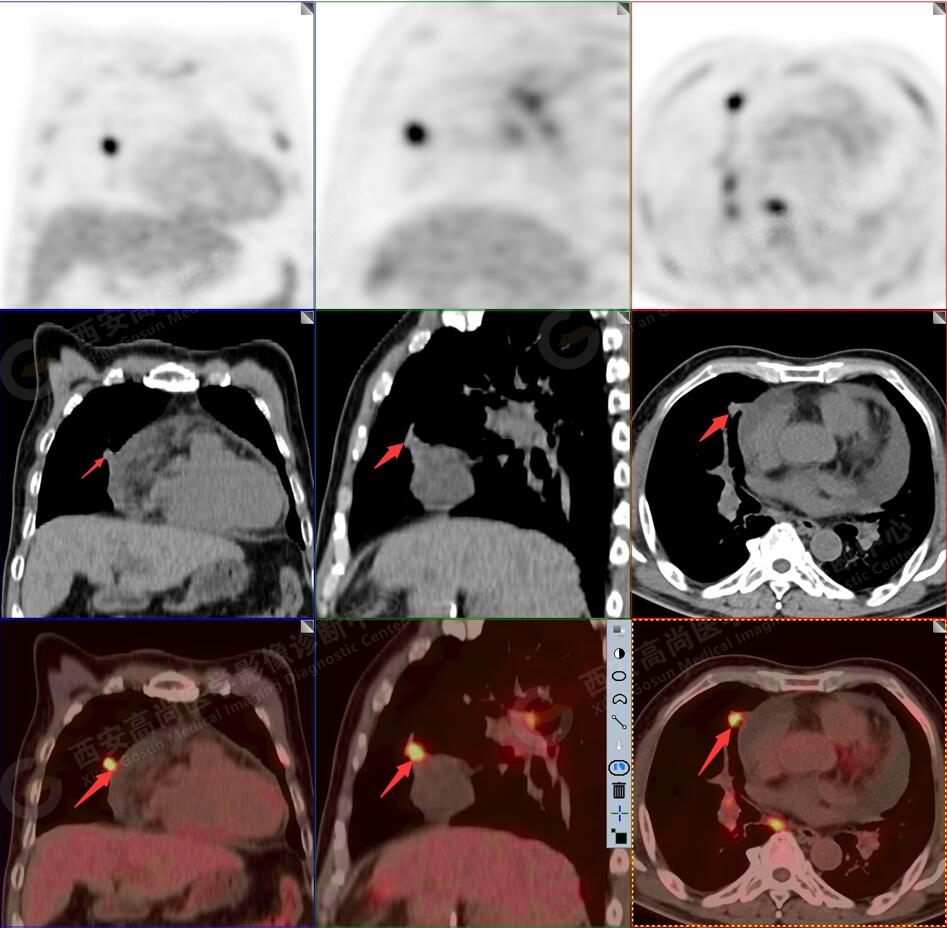

2.以下為全身多發(fā)轉移灶

3.右側頸部(Ⅱ-Ⅴ區(qū))、右側腋窩區(qū)、右側肺門及縱隔(1R、1L、2、4、6、7組)、肝門區(qū)多發(fā)腫大淋巴結,呈不同程度異常增高,均考慮為淋巴結轉移。

4.肝S4、8段團塊狀及結節(jié)狀低密度病變,以S4段病變?yōu)橹什煌潭菷DG代謝異常增高,考慮為肝多發(fā)轉移。

5.右側肱骨上段、左側肩胛骨、右側鎖骨胸骨端、胸骨、雙側多發(fā)肋骨、脊柱多發(fā)椎體及附件、雙側髂骨、雙側髖臼、雙側恥骨、雙側肱骨上段多發(fā)成骨性病變,呈不同程度FDG代謝異常增高,考慮為多發(fā)骨轉移瘤。